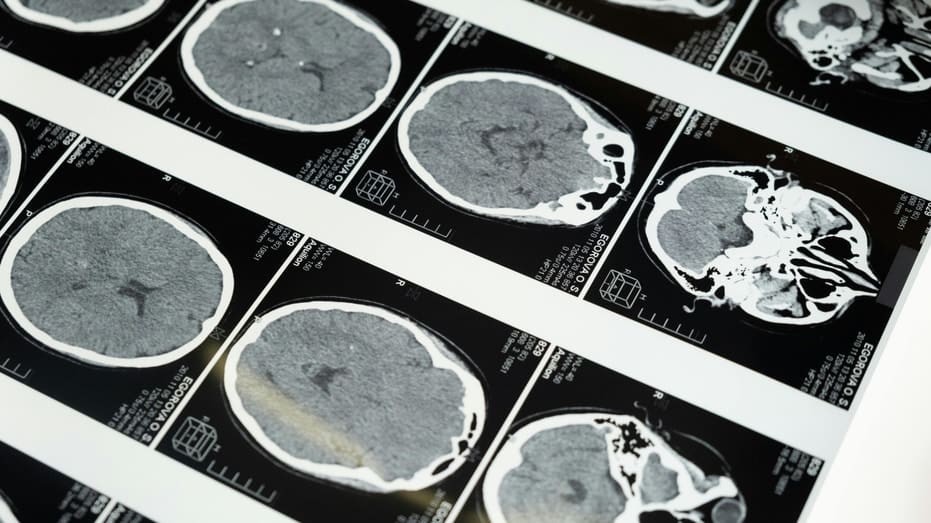

Most brain-computer interface systems rely on electrodes that detect electrical signals from neurons. Neuralink is the most visible example. It places tiny threads inside the brain to record activity. Ultrasound works differently.

Focused ultrasound treatments are already approved for Parkinson’s disease, uterine fibroids and certain tumors. That clinical history gives companies like Gestala a foundation to build on. However, studying or interpreting brain signals with ultrasound is far more complex than delivering targeted stimulation.

Gestala’s first product is focused on chronic pain. The company plans to target the anterior cingulate cortex, a brain region linked to the emotional experience of pain. Early pilot studies suggest that stimulating this area can reduce pain intensity for up to a week in some patients. The first-generation device will be a stationary system used in clinics. Patients would visit a hospital for treatment sessions. Later, the company plans to develop a wearable helmet designed for supervised use at home. Over time, Gestala says it wants to expand into depression, other mental health conditions, stroke rehabilitation, Alzheimer’s disease and sleep disorders. That is an ambitious roadmap. Each condition involves different brain networks and clinical hurdles.

Ultrasound faces technical limits. First, the skull weakens and distorts sound waves. That makes it harder to obtain precise signals. In research settings, detailed readouts of neural activity have required special implants that allow ultrasound to pass more clearly than bone.

Second, ultrasound measures changes in blood flow. Blood flow shifts more slowly than electrical firing in neurons. That delay may limit applications that require fast, detailed signal decoding, such as real-time speech translation. In short, stimulation is one challenge. Accurate readout is another level entirely.